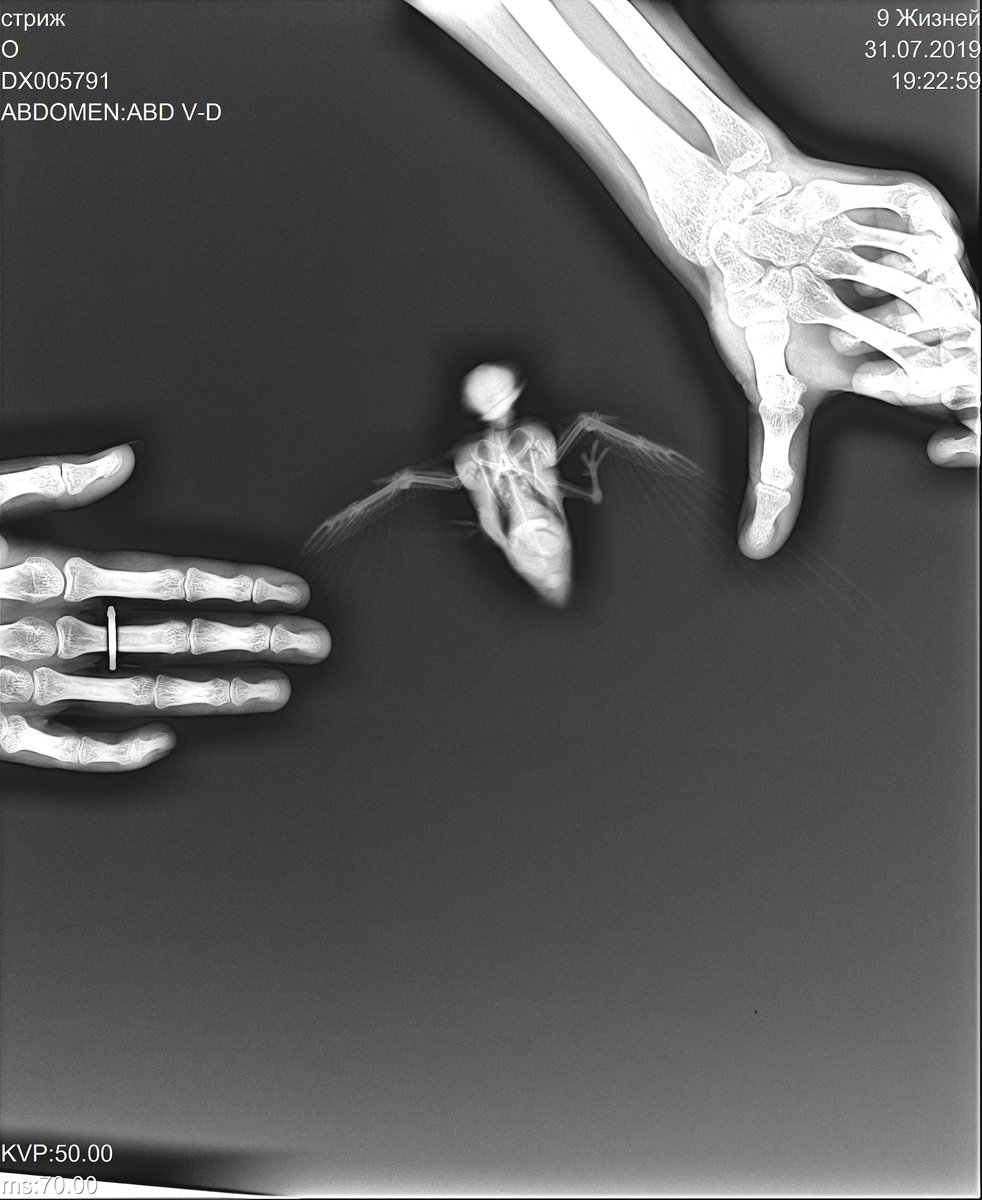

Помогите, пожалуйста. Это мой второй птенец стрижа, вот так повезло, что уже второй раз за лето подбираю. Первый успешно улетел, а со втором до сих пор проблемы. Даже не знаю, что делать. Сначала у птенца были проблемы с крылом, он его волочил, старался не опиратся на него, первоначальный вес был аж 34 грамма, я начала постепенно его выкармливать, ведь он дрожал, был холодным. Постепенно стриж шел на поправку (кормила сверчками домовыми мороженными, предварительно чистила их, так же добавляла в рацион мраморных тараканов). Еще купили травматин, давали по капле два раза в день, сделали рентген, переломов нет, скорее всего ушиб - т.к. птица уже расправляет урыло и держит его почти так же, как и здоровое, не волочит (только в очень редких случаях). Кушаем мы все время принудительно, хотя иногда случаются прорывы и мы даже заглатываем пищу сами, не приходится ее пихать глубоко в горло. Как только вынимаю из коробки птица сразу начинает активно пытатся куда-то уползти, но я ее не пускаю, кормлю в полотенце. Но сейчас вечером она вроде начала засыпать, а потом вновь шебуршала в коробке, скреблась. Я проверила, и вижу совершенно разный стул - белый, жидковатый, несколько штук, кое где виднеется темная змейка. Потом, более свежее что-то похожее на капсулку. Начала проверять, что случилось, она выдала просто темный комочек без белой части и с жидкостью. Понюхала весь помет - резкого запаха нет, только влажным полотенцем пахнет, и может чуть чуть насекомыми. Подскажите пожалуста, это может быть инфекция? Что делать?

Еще прикрепляю рентген, вдруг что-то просмотрели, и фото самой птицы. (Вес сейчас 38 г, взвесила только что)